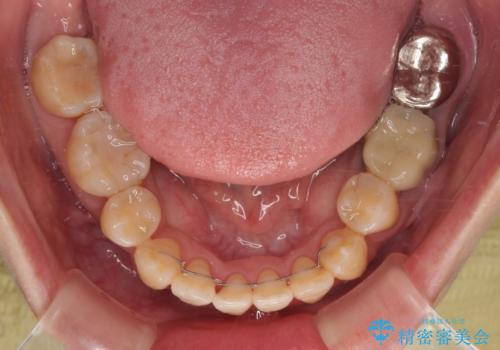

それでも当初とは比べものにならないほど、綺麗な歯列に仕上げることができました。

歯根露出が顕著であったため、歯の移動は早く、スムーズに治療を終えられるかと思いましたが、歯槽骨が硬く、治療は長期間に及びました。

過剰に力をかけ続ける事態となり、一部の歯では変色したり、神経が失活したりとトラブルが続きました。